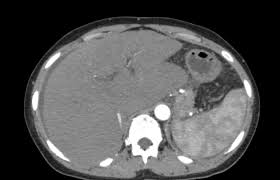

Chiasmata -mə-tə or chiasmas also chiasms 1. Esophageal varices are extremely dilated sub-mucosal veins in the lower third of the esophagus. Located in metro Denver northern Colorado and western Nebraska serving all of the Front Range our team consists of board-certified and fellowship-trained interventional radiologists. This results in hepatic congestion similar to Budd-Chiari syndrome and post-sinusoidal portal hypertension. The patients condition should be monitored throughout the procedure. They are most often a consequence of portal hypertension commonly due to cirrhosis. Toxic injury to liver sinusoids causes sloughing of endothelial cells that embolize to hepatic venules and cause eventual fibrosis of the venules. Coin in the Esophagus. There is no clear consensus regarding the number of occluded veins some authors claim that there should be at least one occluded hepatic vein 7 others state that there are no significant.

Carcinoma of the Colon. Budd-Chiari syndrome a blockage in one or more veins that carry blood from the liver back to the heart. And coumarin skin necrosis adrenal gland hemorrhage and infarction. Toxic injury to liver sinusoids causes sloughing of endothelial cells that embolize to hepatic venules and cause eventual fibrosis of the venules. Chiari malformation CM is a structural defect in the cerebellum characterized by a downward displacement of one or both cerebellar tonsils through the foramen magnum the opening at the base of the skull. Embolism and thrombosis of. La présence dune ou plusieurs affections prothrombotiques est fréquente La prise en charge repose sur un traitement anticoagulant précoce le traitement de l.